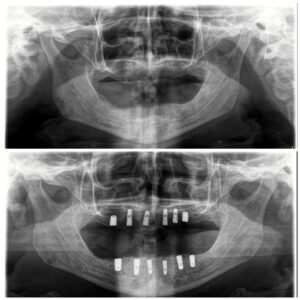

تضيف اجهزه البانوراما الداخلية واجهزة التصوير ثلاثية الأبعاد بعدًا آخر لتقنية الزرع من خلال صورها الدقيقة للفك والأسنان. هذه الدقة ضرورية لتخطيط ووضع الغرسات. يوفر تقييمًا دقيقًا للبنى التشريحيه مثل الأعصاب وجذور الأسنان والجيوب الفكية ومعرفة طبيعة العظم وكثافة وما إلى ذلك ، مما يمنع أي احتمال للفشل الذي يحدث بسبب التشخيص الخاطئ. تم تجهيز مراكز الزرع لدينا بهذه الآلات المتطورة ، مما يمكننا من تنفيذ كل حالة من حالات الزرع بدقه عاليه وأعلى درجات النجاح.